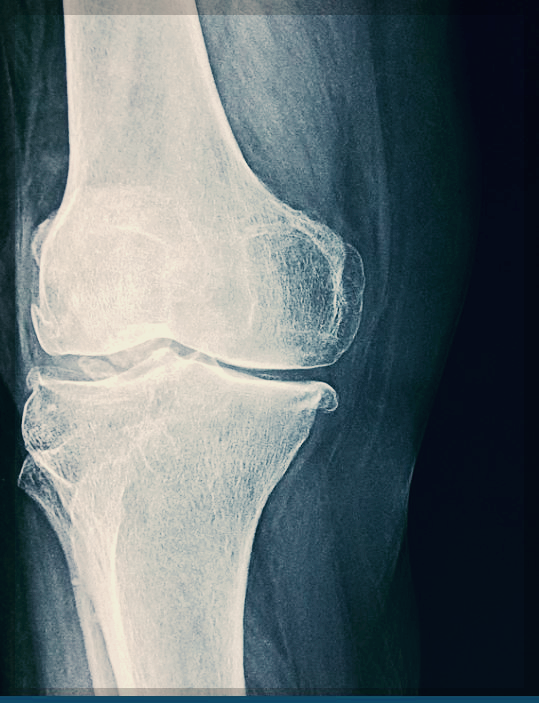

4. 연골재생

무릎 연골의 경우는 손상이 되면 다시 재생되지

않는다고 합니다.

나이가 들면 자연스럽게 콘드로이친이 감소하게 되는데

중년의 나이가 되면, 콘드로이친을 만들 수 있는 양도

굉장히 적습니다.

그래서 콘드로이친 성분을 따로 섭취해 주는 게 좋습니다.